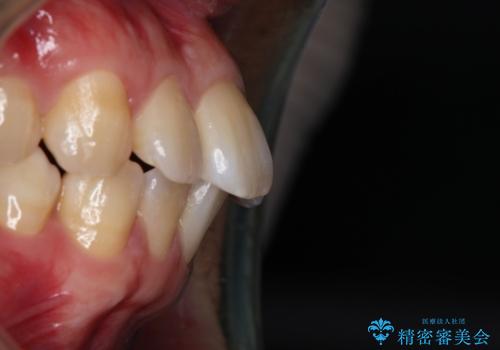

- 上の歯が出ているのが気になるのを主訴にご来院されました。人前で話すお仕事をされており目立たないマウスピース治療を希望されていました。

口元のEラインは気にならないとのことだったのでインビザラインにて治療していくことにしました。

IPR(歯と歯の間を削る処置)と歯列拡大をすることで前歯を少し下げ、がたつきを改善していく治療計画を立てました。

上の前歯が出ているという主訴が綺麗に改善されました。

その他の部位のがたつき、奥歯の噛み合わせも以前と比べると良くなっています。